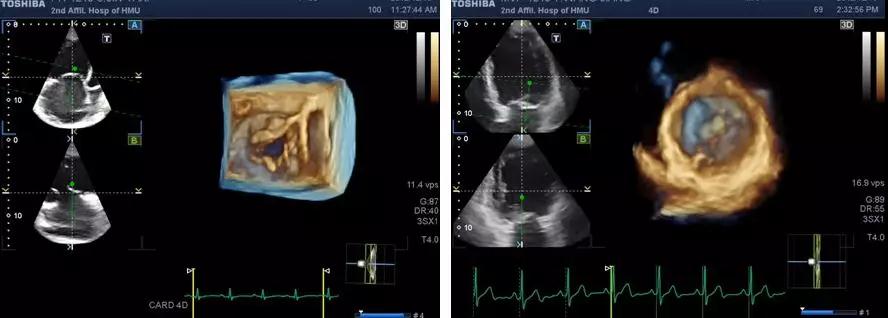

技术名称:实时三维(四维)超声心动图新技术

心血管内科的一项新技术,即实时三维(四维)超声心动图自动左室容积测定(4D auto LVQ)技术被采用。该项检查可清晰展示左室室壁瘤和瘤颈的形态,大小和位置,给心外科医生直观感受,可更准确的计算左室容积,LVEF。术前还通过4D auto LVQ方法,假设部分室壁瘤被切除,计算了剩余左室舒张末容积约为206ml,有明显减少,预测LVEF为44%,有明显提高,为心外科医生提供了手术效果预判断。

实时三维(四维)超声心动图技术采用计算机技术在采集多切面二维图像的同时即刻合成获得心脏立体结构图像,并且360度旋转全方位显示心脏各个角度形态。

实时三维(四维)超声心动图采用先进的计算机技术,四维探头同时获得多个心脏切面,即刻合成呈现心脏立体结构,使心脏结构显示更直观,心脏容积和功能评价也更准确。对心脏外科医生提供了更好的方法在手术前了解结构性心脏病异常结构的形态、大小、相对位置。